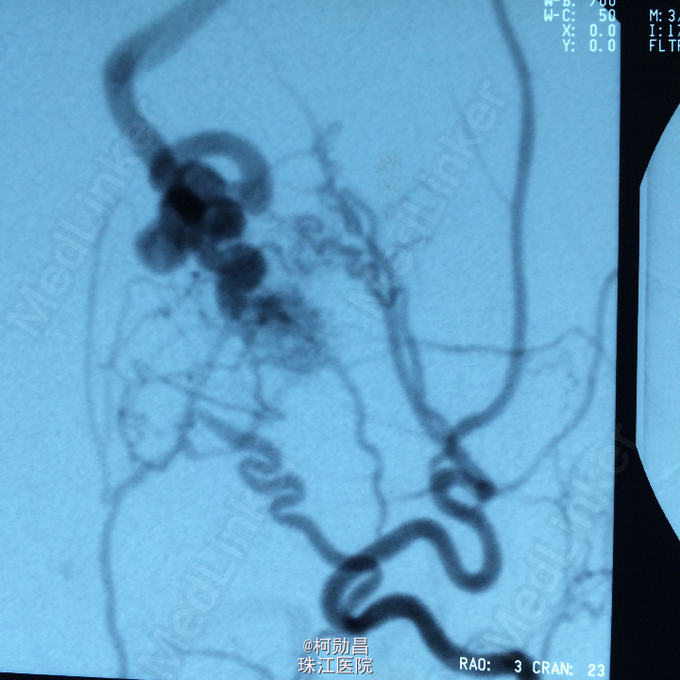

查体:神经系统检查无明显阳性体征。 全脑DSA提示为左枕硬脑膜动静脉瘘

诊断:左枕硬脑膜动静脉瘘 处理:行DSA明确诊断,并予血管内栓塞治疗